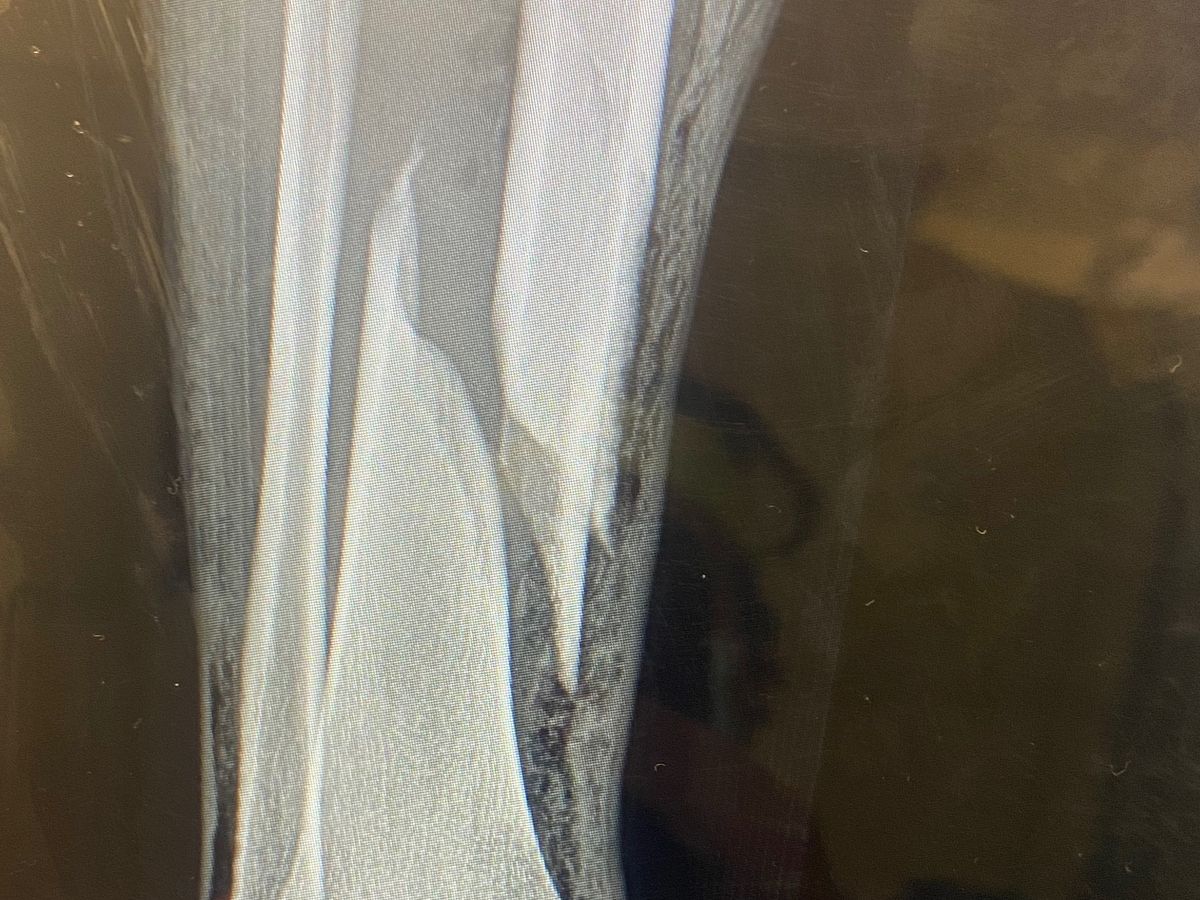

The three guys later to be identified, followed her over to me. There was words exchange. They were aggressive from the start, asking how I knew her. I said I don’t know her but she clearly doesn’t wanna go with you guys. More words then. She pushed one of them. Then they pushed her back into me and the I got hit in the face by two people. I swung back at one the other then smashed my head off a car. I think went out for a second. Came to being kicked more times then I can remember. Someone came to my help, he hit one of them with a bat. Two of them went at him for a second. Then the main guy came back to punching me while I was on the ground. At this point or just before that i was told by someone who saw it all that the main aggressor stomped on my leg when I was already down and out. He then got hit again by a bystander to help me and then I think it was over. When I came to, I saw my bone sticking out of my leg. I screamed and pushed it back in. Then someone helped get my shoe off and the bone came back out. I pushed it in again and passed out. Woke up in the ambulance, then again in the hospital for emergency surgery. I don’t have health insurance so they only kept me in the hospital for 2 1/2 days. Then a stranger help me to an Airbnb. Where I stayed for two more days.i would love to send her something for being so kind to help me when I needed it most. Then i had to pay for a friend to take off work and he had to Fly down from New York ,where I’m from, to drive me in the back of the van home , as I can’t be in an airplane through the possibility of blood clots. This ride is while I’m making this go fund me as it’s all setting in how much this will cost me and how much time I’m going to lose. With work, with my son and the vacation I wanted to take him this summer is now ruined.

i have two black Eyes, bruised ribs, about 20 bruises across my body. My neck head and jaw hurt. It hurts to swallow, But of course worst of all. The double Compound fracture of my tibia and Fibia. Now my back from laying here for 5 days and counting :(